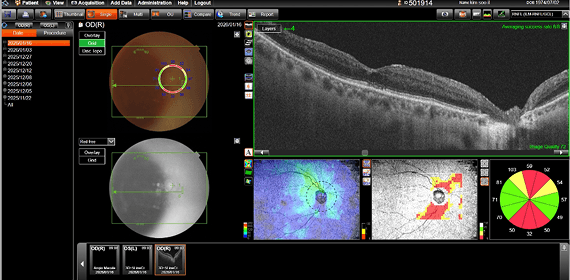

수술 전후의 객관적인 검사 결과를 통해

강남도쿄안과의 정교한 진료를 직접 확인해 보세요.